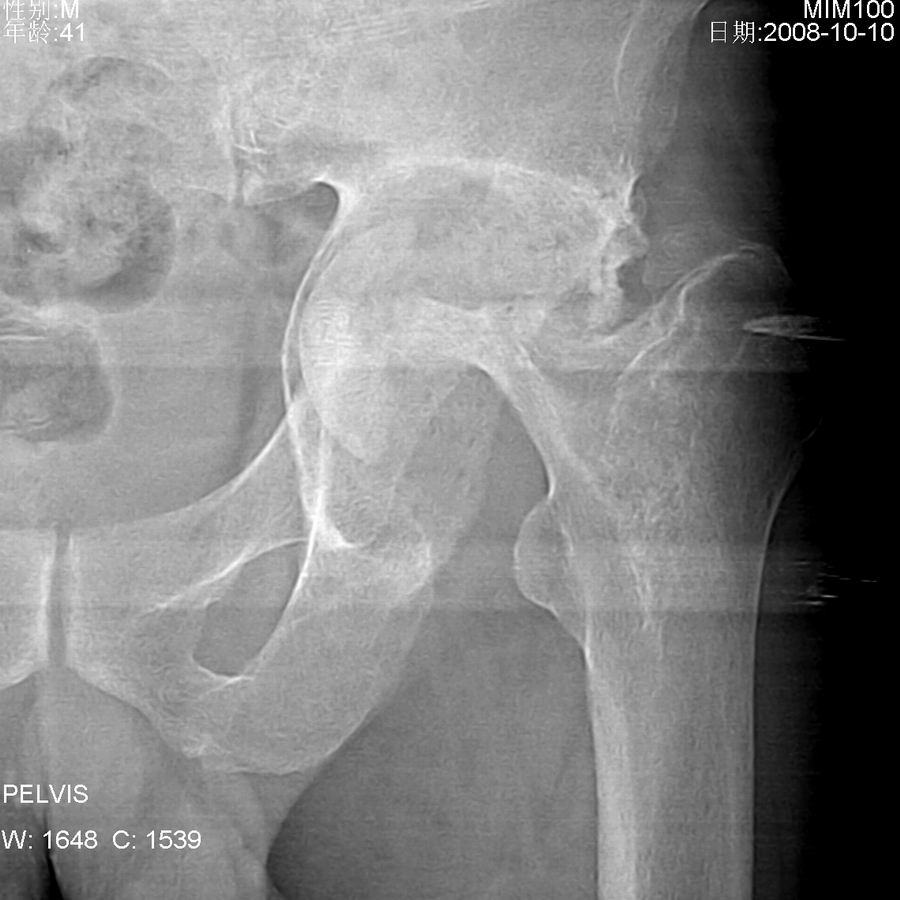

左髋关节疼痛,活动受限。

左髋臼增大,臼底变浅,股骨头及股骨颈骨质破坏并病理性骨折,臼上缘软组织内见机化样影,没见过这种改变,病史不祥,考虑左髋感染性病变可能,期待结果。

结果:髋关节结核

左髋臼增大,臼底变浅,股骨头及股骨颈骨质破坏并病理性骨折,臼上缘软组织内见机化样影,没见过这种改变,病史不祥,考虑左髋感染性病变可能[结核可能性大],期待结果。

左髋臼增大股骨头及股骨颈骨质破坏上缘软组织内见机化样影 , 髋关节结核